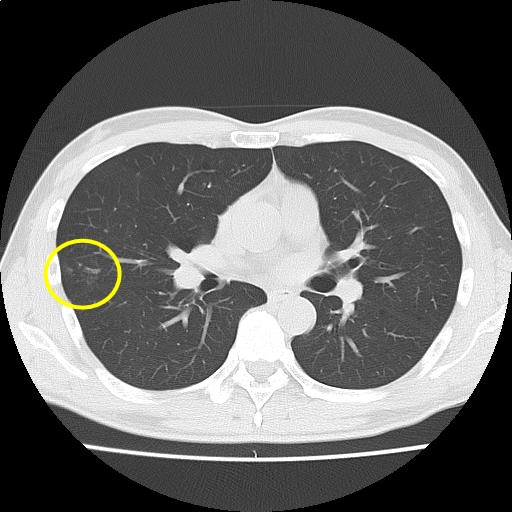

CT画像47

(45/225)